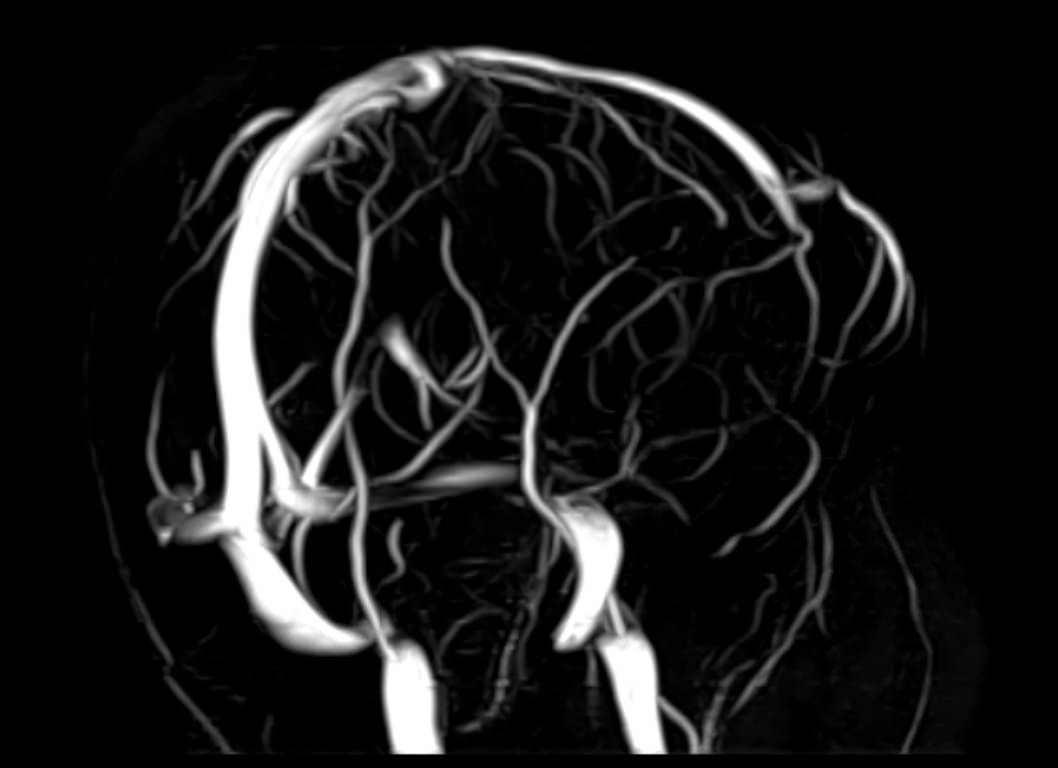

Стандартная МРТ головного мозга дает важную информацию о состоянии и структуре мозговой ткани для выявления большого числа заболеваний, в том числе опухолевых образований, демиелинизирующих заболеваний, воспалительных процессов головного мозга и мозговых оболочек. Стандартную МРТ головного мозга дополняет МР-ангиография, которая отображает состояние артериальной системы кровоснабжения головного мозга. МР-венография головного мозга позволяет детально изучить особенности анатомического и функциональной состояния венозного русла головного мозга.

Компьютерная программа обрабатывает данные, полученные при сканировании, и формирует объемные изображения как самого мозга, так и сосудистой системы в отдельности без прилегающих тканей. Обе методики применяются одновременно и взаимодополняют друг друга, давая полную диагностическую картину.